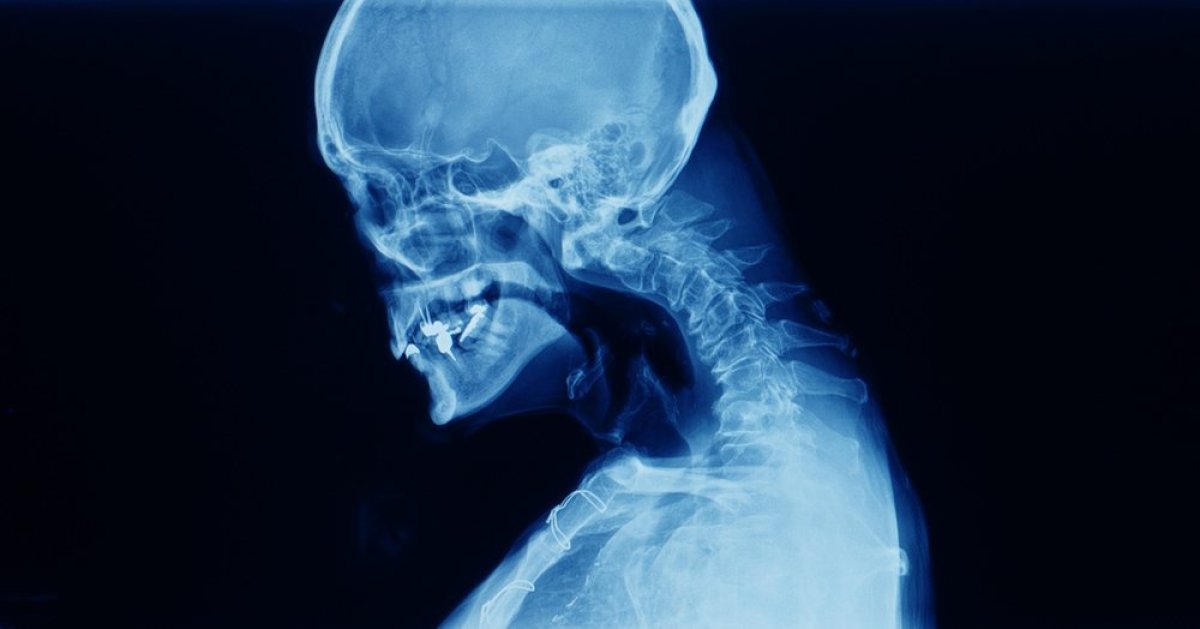

Stanje koje, iako možda ne zvuči previše ozbiljno, značajno utiče na kvalitet života.

Ovaj sindrom nije samostalna bolest, već simptom, odnosno posledica oštećenja ili slabosti određenih mišića vrata.

Specifično, reč je o ekstenzornim mišićima vrata, onim mišićima koji su zaduženi za držanje glave uspravno i povlačenje unazad.

Kada vam mišići oslabe, glava nema adekvatnu podršku i gravitacija je jednostavno "vuče" dole.

Sindrom padajuće glave najčešće se javlja kao komplikacija ili simptom drugih, već postojećih neuroloških ili mišićnih oboljenja. Neki od najčešćih uzroka su:

Neurodegenerativne bolesti

Bolesti poput parkinsonove bolesti, ALS-a (Amiotrofična lateralna skleroza) ili multiple skleroze mogu uticati na nerve koji kontrolišu mišiće vrata, što dovodi do njihove slabosti.

Mišićne bolesti

Različite miopatije (bolesti mišića), uključujući i one inflamatorne (poput polimiozitisa ili dermatomiozitisa) ili mišićne distrofije, direktno slabe vratne mišiće.

Neuropatije

Oštećenja nerava koji inervišu mišiće vrata mogu takođe uzrokovati slabost.

Autoimune bolesti

Ponekad, autoimuni poremećaji mogu napasti mišiće ili nerve, dovodeći do ovog sindroma.

Starija životna dob: Degenerativne promene na kičmi i prirodno slabljenje mišića kod starijih osoba takođe mogu doprineti razvoju.

Glavni simptom je, naravno, nesposobnost držanja glave uspravno.

Pacijenti često moraju da je podupiru rukama, koriste bradu kao oslonac ili da se naginju unazad da bi održali pogled usmeren napred.

Ovo stanje dovodi do niza problema:

Lečenje sindroma padajuće glave usmereno je prvenstveno na lečenje osnovne bolesti koja ga uzrokuje.

Pored toga, primenjuju se i simptomatske terapije kao što su fizikalna terapija, koriste se ortopedska pomagala, rade se vežbe za jačanje preostalih mišića i poboljšanje držanja, piju se lekovi za smanjenje bola.

U retkim i pažljivo odabranim slučajevima, kada konzervativne metode ne pomažu, hirurška intervencija može biti opcija za stabilizaciju kičme.

Sindrom padajuće glave je kompleksno stanje koje zahteva multidisciplinarni pristup.

Iako može biti frustrirajuće i ograničavajuće, razumevanje uzroka i dosledna terapija mogu značajno poboljšati kvalitet života pacijenata.